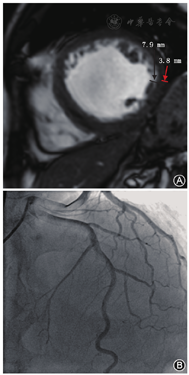

两组患者冠状动脉LAD管腔均未见狭窄,其中DCM 35例,LVEF为24.1%±8.7%,心肌局部肌小梁稍增多(图1A),年龄(53.9±10.8)岁,男性31例(88.6%),心肌过度小梁化26例(74.3%,26/35),其中5例受累节段大于3个,间隔支稀疏(图1B),平均间隔支支数为3.5支,28例LAD慢血流;LVNC 17例,LVEF为32.3%±16.1%,左心室弥漫性海绵样心肌(图2A),其中8例受累节段大于4个,平均年龄(58.4±10.1)岁,男性9例(52.9%),间隔支显影良好(图2B),平均间隔支支数为6.5支,2例表现为LAD慢血流。两组LVEF差异有统计学意义(t=2.386, P=0.021),LVNC组LVEF明显高于DCM组;两组间慢血流差异有统计学意义(t=8.423,P<0.000 1),DCM组LAD血流明显慢于LVNC组;经秩和检验,两组间隔支数差异有统计学意义(P<0.05),且LVNC组间隔支支数为DCM间隔支支数的1.9倍。

心肌慢血流现象其实并不少见,在疑似冠心病患者人群中,大约有7%的患者心外膜下冠状动脉正常,但存在慢血流现象[11],主要原因归因于心肌微循环功能障碍[12,13,14]。研究表明,DCM常伴随心肌弥漫性炎性细胞浸润[15,16],包括左心室间壁心肌的炎性细胞浸润和反复损伤修复累及微小血管,从而导致间隔支血管稀疏,而LVNC主要累及中部、心尖部左心室侧壁、前壁、下壁,很少累及室间隔,因此,间隔支受累不明显。本次研究进一步证实,DCM患者间隔支稀疏,且LAD血流表现慢血流有28例,约占80.0%;而LVNC间隔支显影良好,LAD慢血流2例,占11.8%,两组间慢血流差异有统计学意义(P<0.000 1)。可见,DCM患者心肌炎性细胞浸润的同时也累及心肌微小血管,导致微小血管的闭塞。因此,是否具备慢血流很可能是鉴别两种疾病的一个重要证据。另外,本次研究中,通过对间隔支的统计还发现,LVNC患者平均间隔支支数为6.5支,而DCM平均间隔支支数为3.5支,两组差异有统计学意义(P<0.05),且前者是后者的1.9倍。因此,通过对LAD心肌血流及间隔支分布情况的评估,对疾病的鉴别诊断可能起到积极作用。